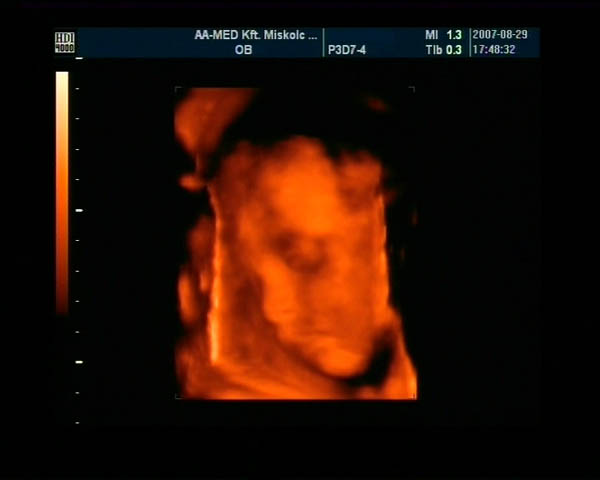

Lilith, nekem a védőnő azt mondta, hogy a 32. héten lesz genetikai uh megint, azaz mi a jövő 7en megyünk, és mi folytatjuk is a 4D-s DVD-t, ha Lizike is most úgy gondolja.

Hogy rohan az idő, már 3 hét el is telt, mert 28 hetesen kezdtük a felvételt ... Már csak 9 hét... Nekem még egy vérvétel is lesz jövő7en, talán vérszegénységet néznek.